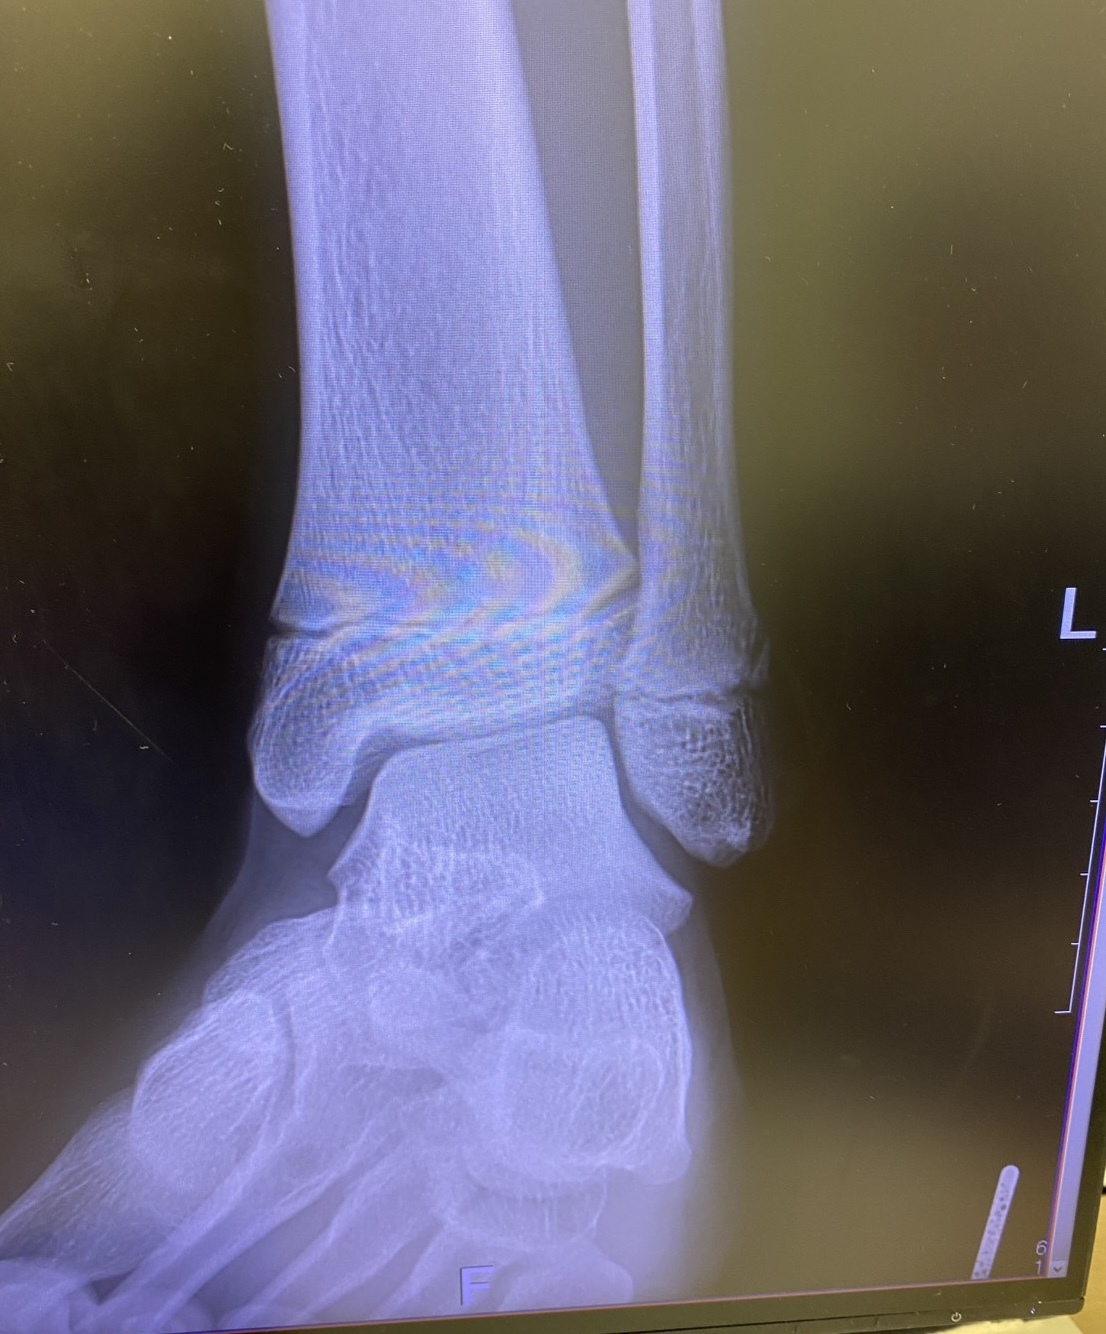

- バレーで足を踏み左足を負傷